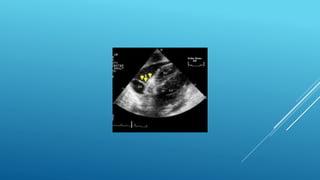

๏‚„ standard transthoracic echo (TTE) is typically

๏‚„ screening modality of choice for LV thrombus

๏‚„ detection and should performed within 24 hours

๏‚„ of admission in those at high risk for apical LV thrombus

๏‚„ (Large or anterior MI or receiving delayed reperfusion).

๏‚„ Contrast TTE or Cardiac MRI should be considered

๏‚„ based on local availability and resources. If ....

๏‚„ (1) LV apex is poorly visualized,

๏‚„ (2) Anterior or Apical wall motion abnormalities are

present

๏‚„ (3) High Apical wall motion scores are calculated

๏‚„ (โ‰ฅ5 on noncontrast TTE)